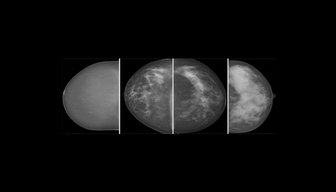

Screening examinations of women with dense breasts classified with automated software resulted in higher recall and biopsy rates and higher odds of breast cancers compared with women with nondense breasts. https://bit.ly/2twL7ux

#breastimagingpic.twitter.com/uliKlI8LWI